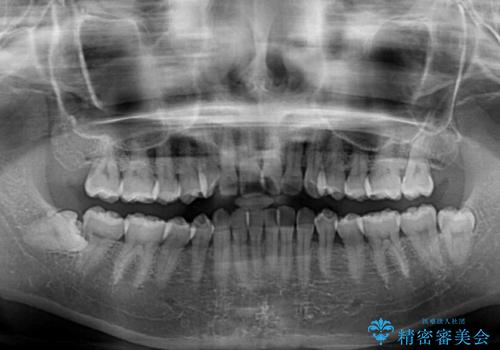

- 上下前歯のデコボコを気にして来院された患者様です。

叢生は軽度で、ワイヤー矯正でもマウスピース矯正でも対応可能な歯列でした。

僅か1年間できれいに歯列を整えることができ、患者様には大変満足していただきました。